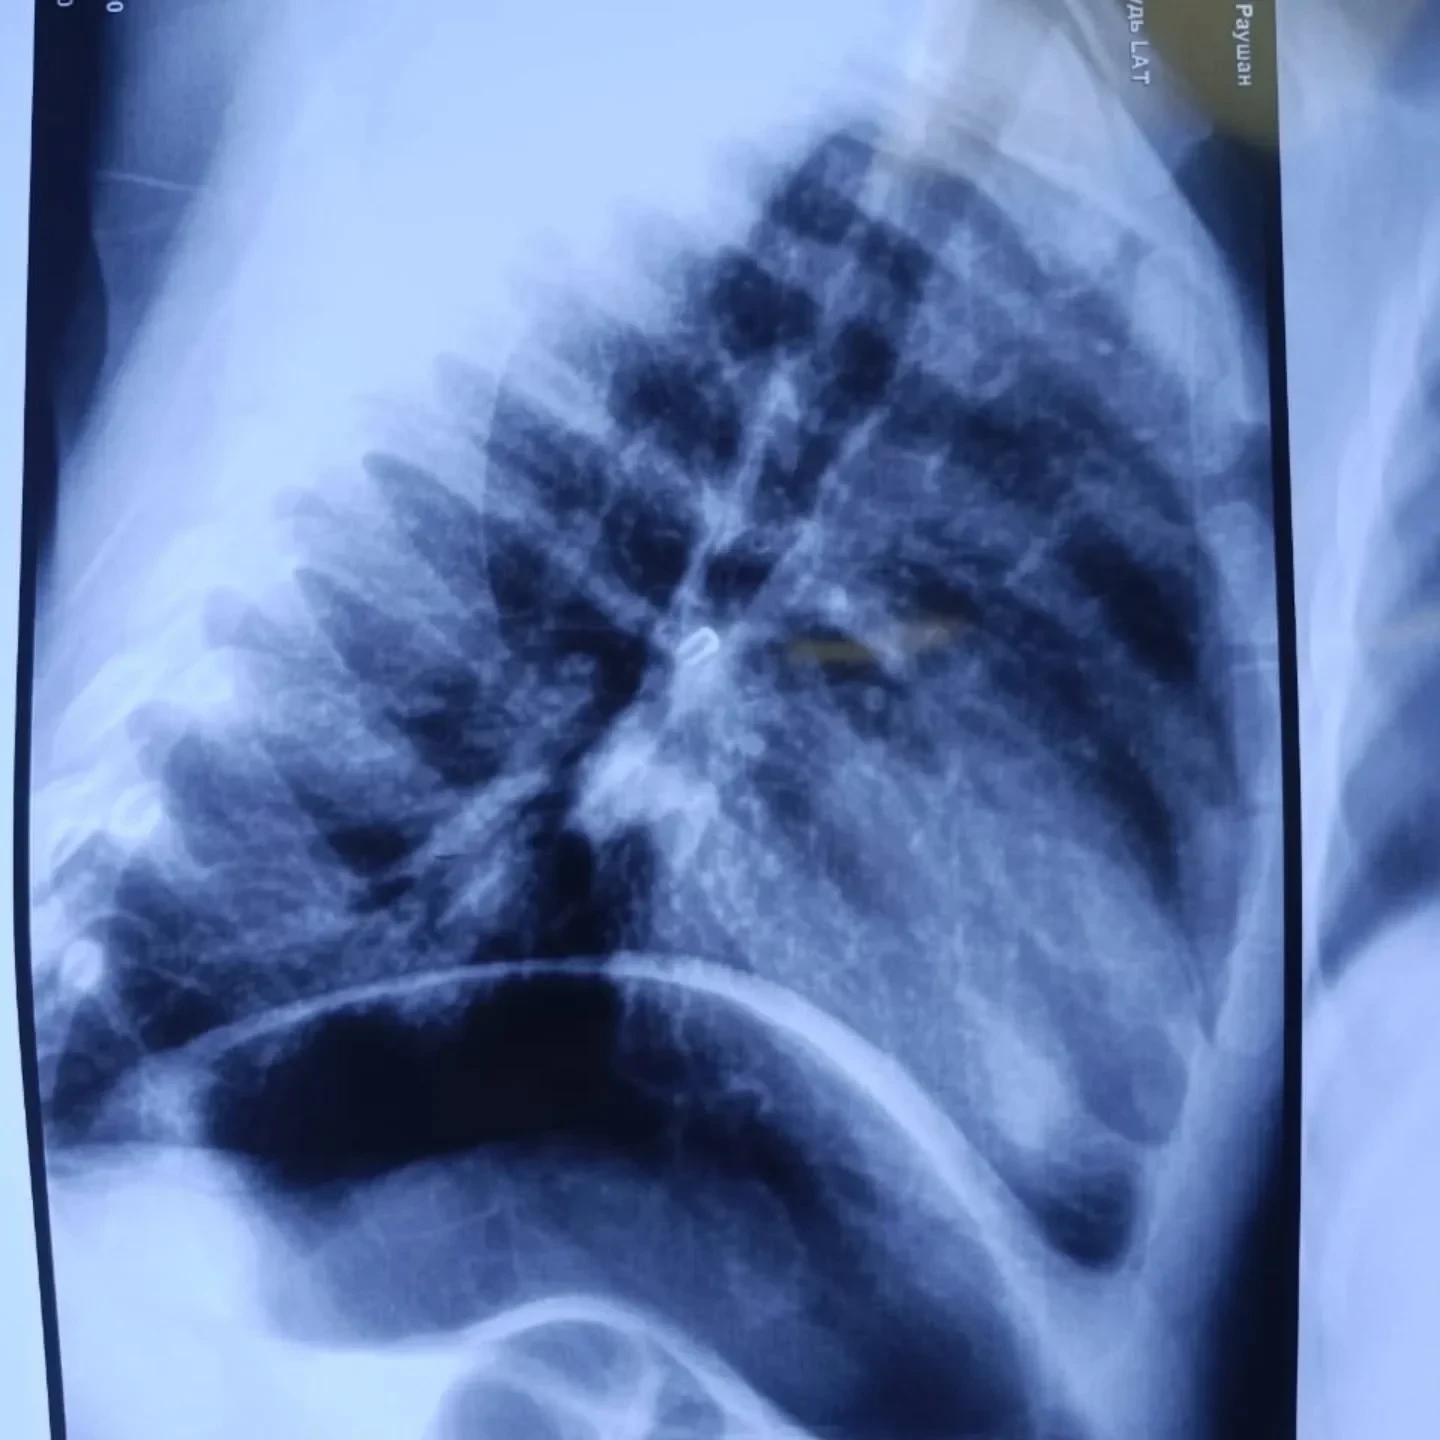

Ооруканага киргенде баланын абалы оор деп бааланган, анткени анын дем алуу жетишсиздиги байкалган. Рентгендик изилдөө оң жактагы негизги бронхта чет элдик дене бар экенин көрсөткөн.

Дарыгерлердин командасы жалпы наркоз астында ригиддүү бронхоскопияны жүргүзүп, кыжырданган предметти ийгиликтүү чыгарган, ал кичинекей мончок болуп чыккан.